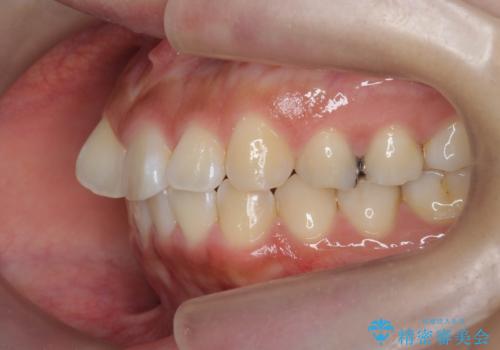

- 前歯の目立つねじれを矯正治療で治したい、と来院されました。

マウスピース矯正を始める前に、ねじれを取るのが短期間で済む部分ワイヤー小矯正を行うことで、全体的な治療期間を短くする治療計画を実行していきます。

前歯のねじれはマウスピース矯正の苦手な動きになり、治療期間が長くなる原因になりやすいです。